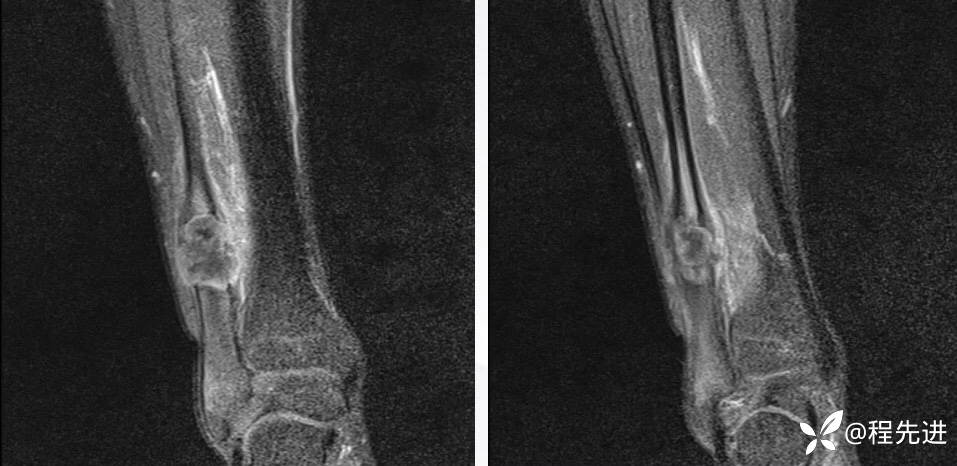

MR

T1+C